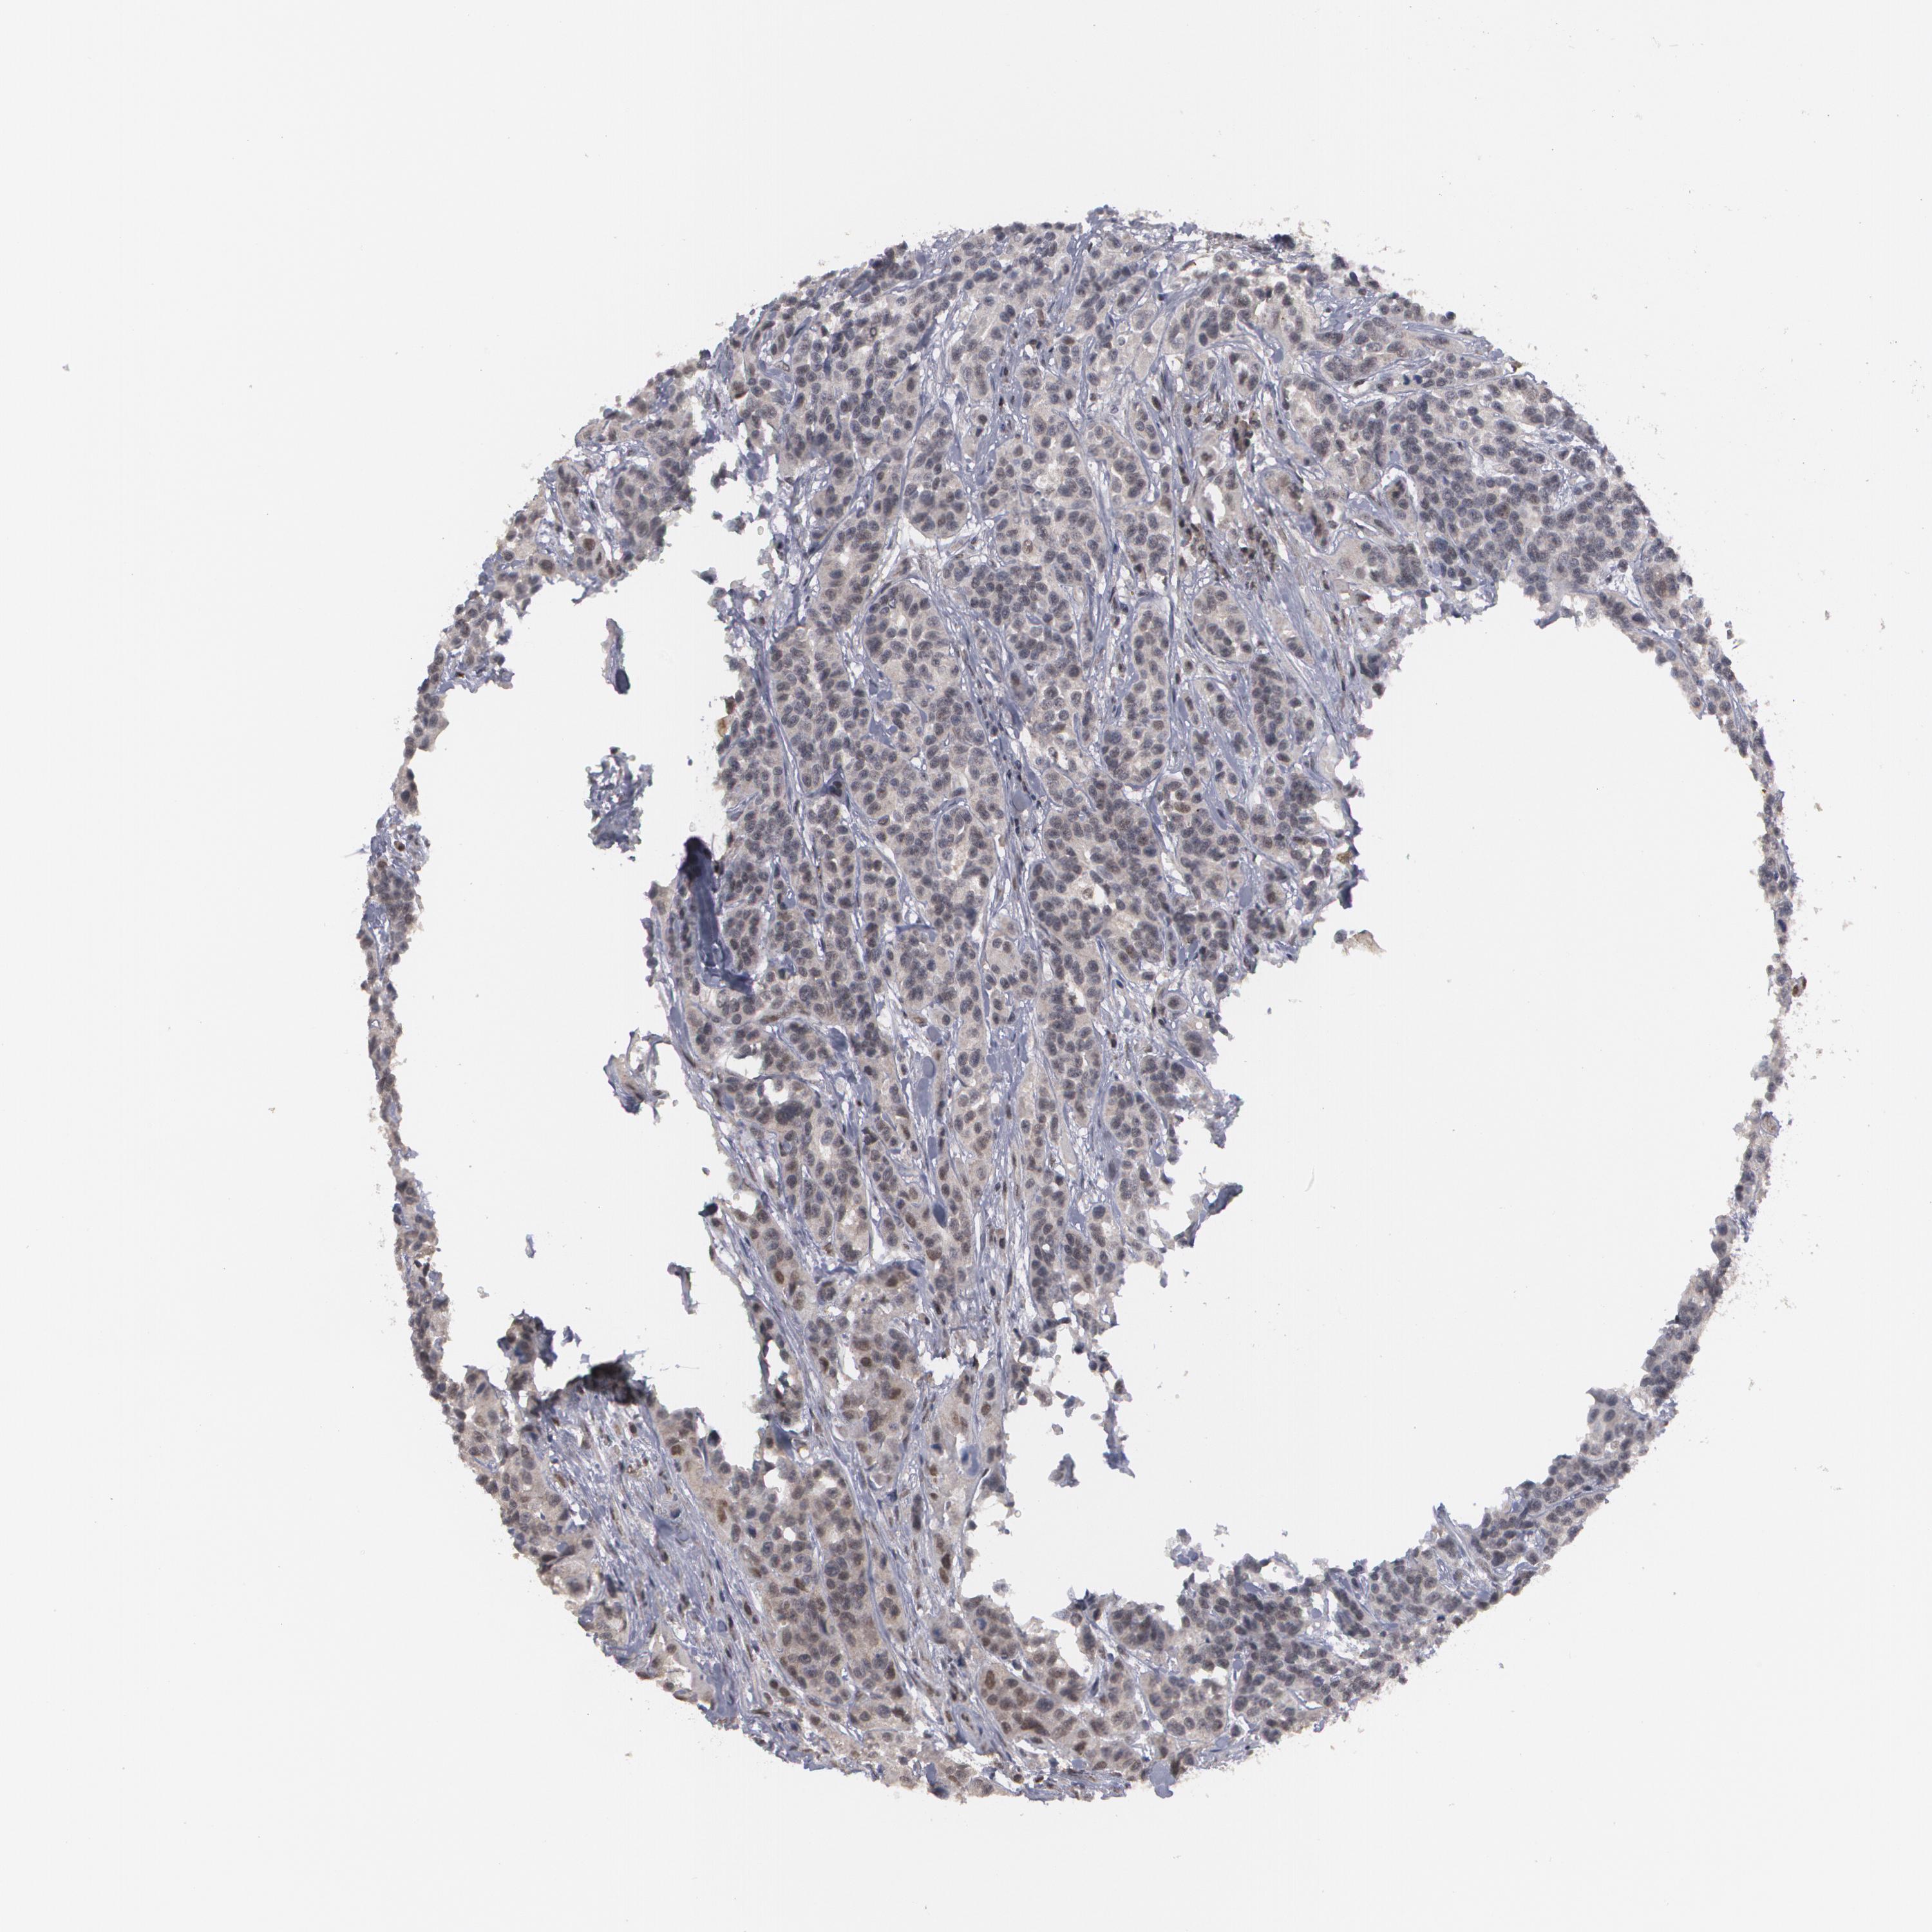

UROTHELIAL CANCER - Protein expressioni

A mouse-over function shows sample information and annotation data. Click on an image to view it in a full screen mode. Samples can be filtered based on level of antibody staining by selecting one or several of the following categories: high, medium, low and not detected. The assay and annotation is described here.

Note that samples used for immunohistochemistry by the Human Protein Atlas do not correspond to samples in the TCGA dataset.

Antibody stainingi

Antibody staining in the annotated cell types in the current human tissue is reported as not detected, low, medium, or high, based on conventional immunohistochemistry profiling in selected tissues. This score is based on the combination of the staining intensity and fraction of stained cells.

Each image is clickable and will lead to virtual microscopy that enables deeper exploration of all samples and also displays staining intensity scores, fraction scores and subcellular localization as well as patient and tissue information for each sample.

Antibody HPA001552

Antibody HPA001846

Urothelial carcinoma, High grade

Urothelial carcinoma, Low grade

Adenocarcinoma, NOS